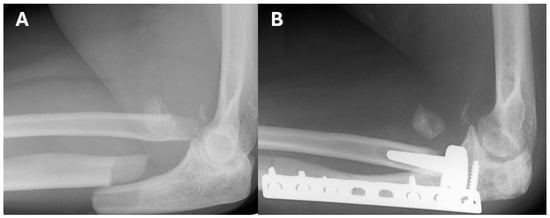

Radiographic analysis of all 14 patients showed varying degrees of implant loosening. In the modular group, eight patients (80%) showed no signs of loosening, one (10%) had mild loosening, and one (10%) had moderate loosening. In the monobloc group, all four patients exhibited loosening, with three (75%) showing mild and one (25%) showing moderate loosening. Mild degenerative changes were observed in two (20%) patients in the modular group and one (25%) patient in the monobloc group. Heterotopic ossification was noted in three patients (30%) in the modular group, none of which were functionally limiting, while no cases were observed in the monobloc group (Figure 2 and Figure 3).

Figure 3. 43-year-old female patient with a comminuted fracture of the radial head and a proximal ulna fracture, who underwent fixation of the ulnar fracture with a plate and screws, and implantation of a monobloc radial-head prosthesis. (A) Lateral radiograph of the right elbow before surgery in 2007. (B) Lateral radiograph in 2018 .In both radiographs (A,B), fragments of the radial head that were left during surgery can be seen.